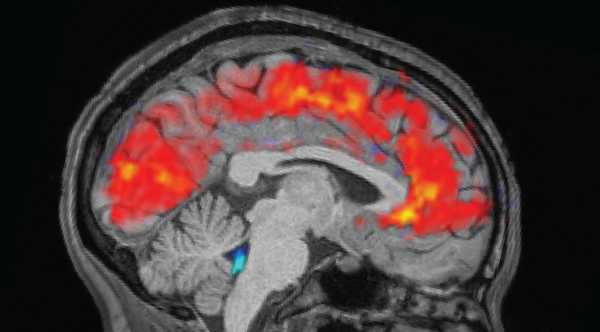

Фізичні вправи корисні для здоров'я мозку, ймовірно, через «бульбашки» речовин, що переносяться кровотоком. (Зображення: Mary Swift/Getty Images)

Фізичні вправи мають велику користь для мозку, але точні причини цього залишаються загадкою. Тепер нові дослідження показують, що тренувані м'язи вивільняють у кров речовини, що стимулюють роботу мозку, — і, принаймні у лабораторних тварин, цей стимулятор може передаватися від однієї особини до іншої за допомогою ін'єкції цих речовин.

Раніше поширені пояснення того, чому регулярна фізична активність корисна для мозку, вказували на кращий кровообіг, менший стрес і міцніше серце. Але ці ідеї не повністю пояснювали, як рух безпосередньо впливає на нейрони.

Підказки з'являються в результаті досліджень на тваринах. У дослідженні, опублікованому в жовтні в журналі Brain Research, одна група молодих дорослих мишей вільно бігала на колесах протягом чотирьох тижнів, тоді як інші залишалися малорухливими. Потім вчені виділили позаклітинні везикули — молекулярні «пакети», що несуть білки та генетичний матеріал — з крові бігунів і ввели їх малорухливим мишам.

Після того, як ці ін'єкції отримували двічі на тиждень протягом чотирьох тижнів, у цих оброблених малорухливих мишей виростило приблизно на 50% більше нових клітин мозку в області, пов'язаній з пам'яттю, яка називається гіпокампом, порівняно з необробленими малорухливими мишами. Більшість нових клітин розвинулися в зрілі нейрони, процес, відомий як нейрогенез. (Щодо людей, точаться дебати щодо того, чи відбувається нейрогенез у значних кількостях у дорослому мозку.)

Перший автор дослідження Меган Конноллі, постдокторант з Університету Альберти, розповіла Live Science в електронному листі, що її вразила специфічність ефекту — везикули, виділені з мишей, що бігають, стимулювали ріст нейронів, тоді як ті, що були виділені з малорухливих тварин, — ні. Дослідники ще не знають, чи везикули потрапляли в мозок, чи діяли опосередковано через інші сигнали організму. Але Конноллі пояснила, що самі везикули несли багато білків, пов'язаних з антиоксидантним захистом та нейрогенезом.

Примітно, що цей сплеск нових клітин мозку може мати значення лише за умови, що ці клітини виживуть достатньо довго, щоб повністю інтегруватися в існуючу структуру мозку, сказав Пол Лукассен, нейробіолог з Амстердамського університету, який не брав участі в дослідженні. Дослідження було зосереджено на «новонароджених нейронах, яким ще потрібні тижні, щоб вирости та підключитися до існуючих ланцюгів мозку», – повідомив він Live Science в електронному листі. «Лише коли вони знайдуть своє місце в мережі, вони зможуть допомогти сформувати навчання та пам’ять».

Конноллі сказав, що наступним кроком є перевірка того, чи можуть ці везикули відновлювати нейрогенез та покращувати пам'ять у лабораторних моделях захворювань мозку — напрямки, які деякі дослідники вже досліджують.

В іншому дослідженні, опублікованому раніше цього року в журналі iScience, вчені використовували добре відому модель хвороби Альцгеймера (ХА) на мишах. При ХА нейрони функціонують неправильно та з часом відмирають, частково через накопичення аномальних білків, включаючи амілоїд і тау-біотик. В експерименті одна група мишей добровільно бігала на колесах протягом шести місяців, тоді як інша група була малорухливою; активні миші показали менше накопичення амілоїду в корі головного мозку та кращий метаболізм і пам'ять, ніж їхні аналоги.

В іншій частині цього дослідження дослідники давали везикули мишей, які щойно займалися спортом, тваринам з малорухливою моделлю хвороби Альцгеймера. Вони виявили, що везикули, що вводилися через ніс, відтворювали метаболічні переваги, але не покращували пам'ять і не знижували рівень амілоїду.

Марк Феббрайо, професор Університету Монаша та член дослідницької групи, пояснив, що метод інтраназального введення міг вплинути на показники пам'яті, оскільки він вимагає легкої анестезії. Він повідомив Live Science в електронному листі, що його група зараз проводить подальші експерименти з учасниками-людьми, порівнюючи везикули, що прямують до мозку та з нього під час фізичних вправ. Попередні результати свідчать про те, що везикули, що прямують до мозку, можуть бути збагачені білками, що впливають на когнітивні функції.

Але везикули можуть бути лише однією частиною цієї головоломки. Інші нещодавні дослідження на людях показують, що регулярні фізичні вправи, ймовірно, допомагають мозку через кілька біологічних шляхів. Як зазначив Йорам Мул, нейробіолог з Амстердамського університету, фізичні вправи активізують усе тіло — м’язи, нерви і навіть кишкові мікроби.

«Це ефект усього організму», — сказав Мул, — «не один фактор пояснює все, а симфонія багатьох факторів і процесів», що грають у ідеальній гармонії.